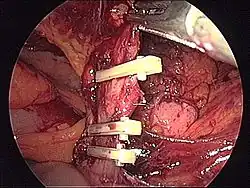

- Schematyczne obrazy jelita grubego i uchyłków esicy i śródoperacyjne obrazy uchyłków i nowotworu jelita grubego

Śródoperacyjny widok nowotworu esicy (operacja laparoskopowa).

- Przykład zespolenia maszynowego i ręcznego

Zespolenie maszynowe (resekcja esicy). Założenie grzybka do proksymalnego odcinka jelita.- Zespolenie maszynowe (resekcja esicy). Założenie aparatu do kikuta odbytnicy – przygotowanie doperforacji szwu maszynowego, które powinno nastąpić centralnie w bezpośredniej bliskości szwu maszynowego.

- Zespolenie maszynowe (resekcja esicy). Sztyft wyprowadzony poza światło jelita. Po usunięciu perforatora (białe ostrze) zostanie połączony z grzybkiem znajdującym się w proksymalnej części planowanego zespolenia.

Zespolenie maszynowe (resekcja esicy). Połączenie grzybka i aparatu z kikuta. Zbliżanie i przygotowanie do zespolenia.- Ręczne zespolenie jelita. Pod jelitem widoczne plastikowe klipsy dla zaopatrzenia naczyń (niebieskie).